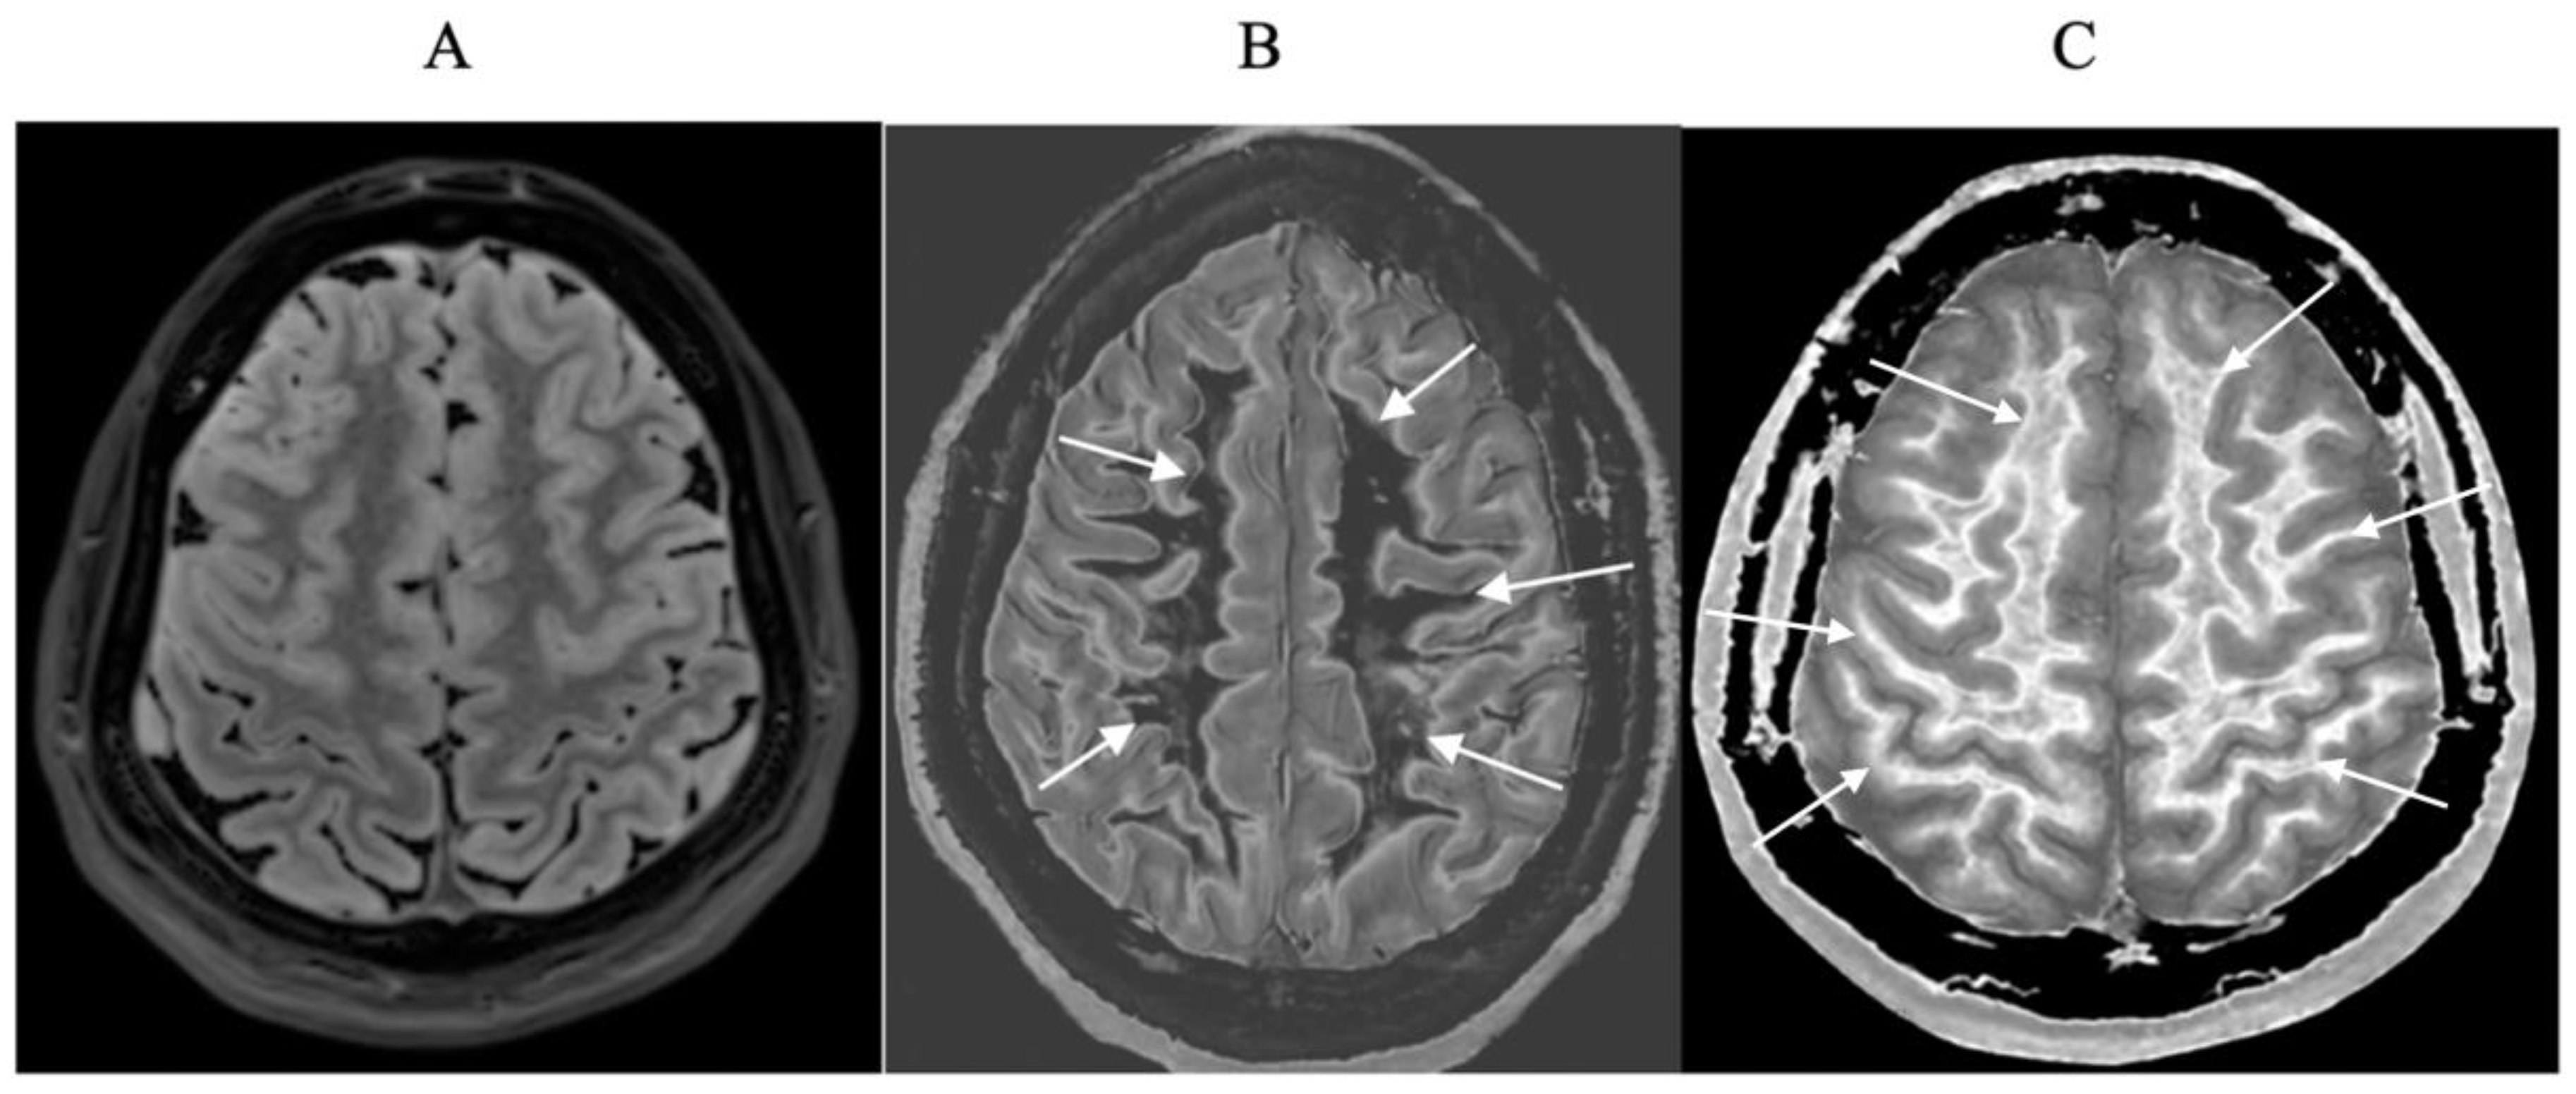

- Ultra-high contrast MRI using bipolar filters (BLAIRs) can show abnormalities with very high contrast where little or no change from normal is seen with common conventional state-of-the-art sequences.

- The abnormalities shown with ultra-high contrast are due to small changes in tissue properties such as T1 and T2 in disease. This is complementary to existing sequences which show abnormalities due to larger changes in T1 and T2 in disease.

- At boundaries between tissues and fluids on ultra-high contrast images there is frequently an increase in contrast and an increase in the spatial resolution of that contrast.

- Extensive abnormalities were seen in mild traumatic brain injury, multiple sclerosis and white matter associated with cerebral tumours in the absence of changes in T2-weighted spin echo or T2-FLAIR images.